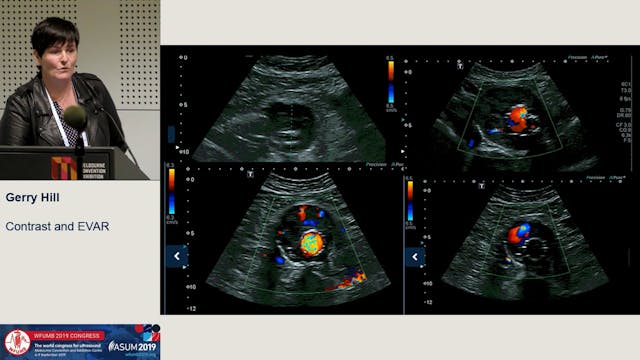

Contrast and EVAR

The use of contrast enhanced ultrasound (CEUS) to quantify the presence or absence of an endovascular leak using ultrasound.